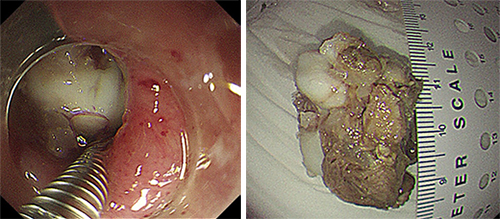

尝试数分钟后,异物取出困难。李宾副主任医师当机立断,在许洪伟主任指导下更换内镜下用的胃石碎石器套取异物。胃石碎石器主要用于粉碎胃内结石,此次并不用于粉碎患者食管内的骨性异物,而是另辟蹊径,应用碎石器前端钢丝套住异物,再绷紧碎石器后端牢牢固定异物,调整牵拉方向,让患者做吞咽动作以松弛食管上段括约肌,成功拖出大小约4.0cm×2.5cm骨性异物。

整个内镜手术过程仅耗时13分钟。因异物过大且嵌顿于食管,碎石器钢丝取出后已弯曲变形,可以推断出普通内镜器械根本无法套取或牵拉住异物。如此大的异物在食管内存留3天,极易出现食管壁缺血、坏死,严重者可能出现食管穿孔。李宾副主任医师再次进入胃镜,发现原食管异物存留的位置,食管黏膜破损、溃疡明显,穿孔不能排除,在许洪伟主任指导下,给予放置胃管,行肠内营养,并协调消化内科病房石秀菊护士长安排患者住院进一步康复治疗。